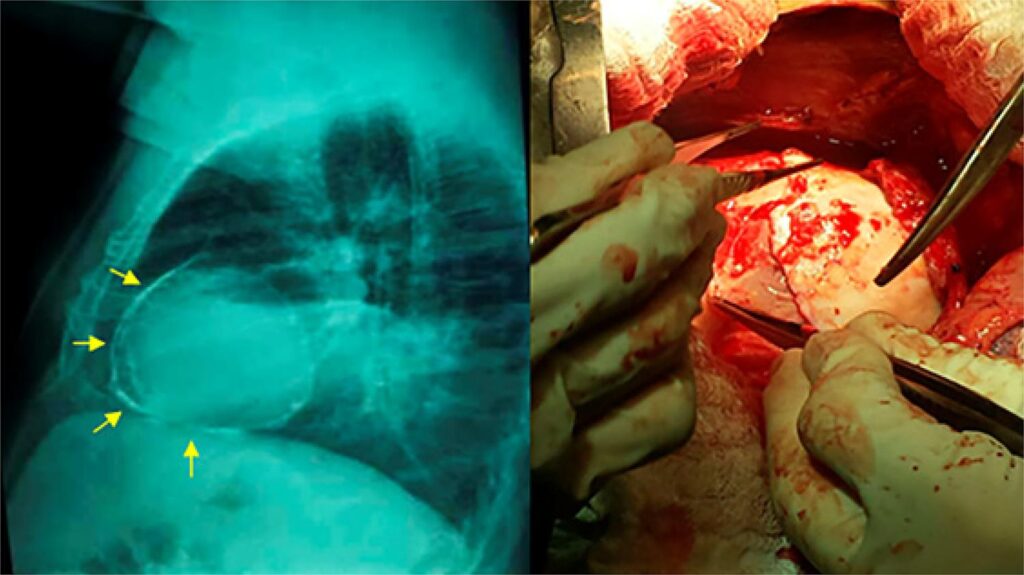

Important Constrictive Pericarditis in a Patient with Schistosomiasis: A Case Report

Schistosomiasis mansoni (SM) is one of the most common causes of pulmonary hypertension and is often associated with the hepatosplenic form of the disease. However, constrictive pericarditis (CP) is not cited in the medical literature as a consequence of SM., One single case report, published in 1979, associating CP with schistosomiasis, presented the etiologic agent of Schistosoma haematobium. The present study described a rare case of CP in a patient with chronic hepatosplenic SM, with a significant improvement in the parameters of ventricular filling and myocardial deformation after surgery, illustrating the importance of the echocardiogram in the detection of complications caused by this disease.